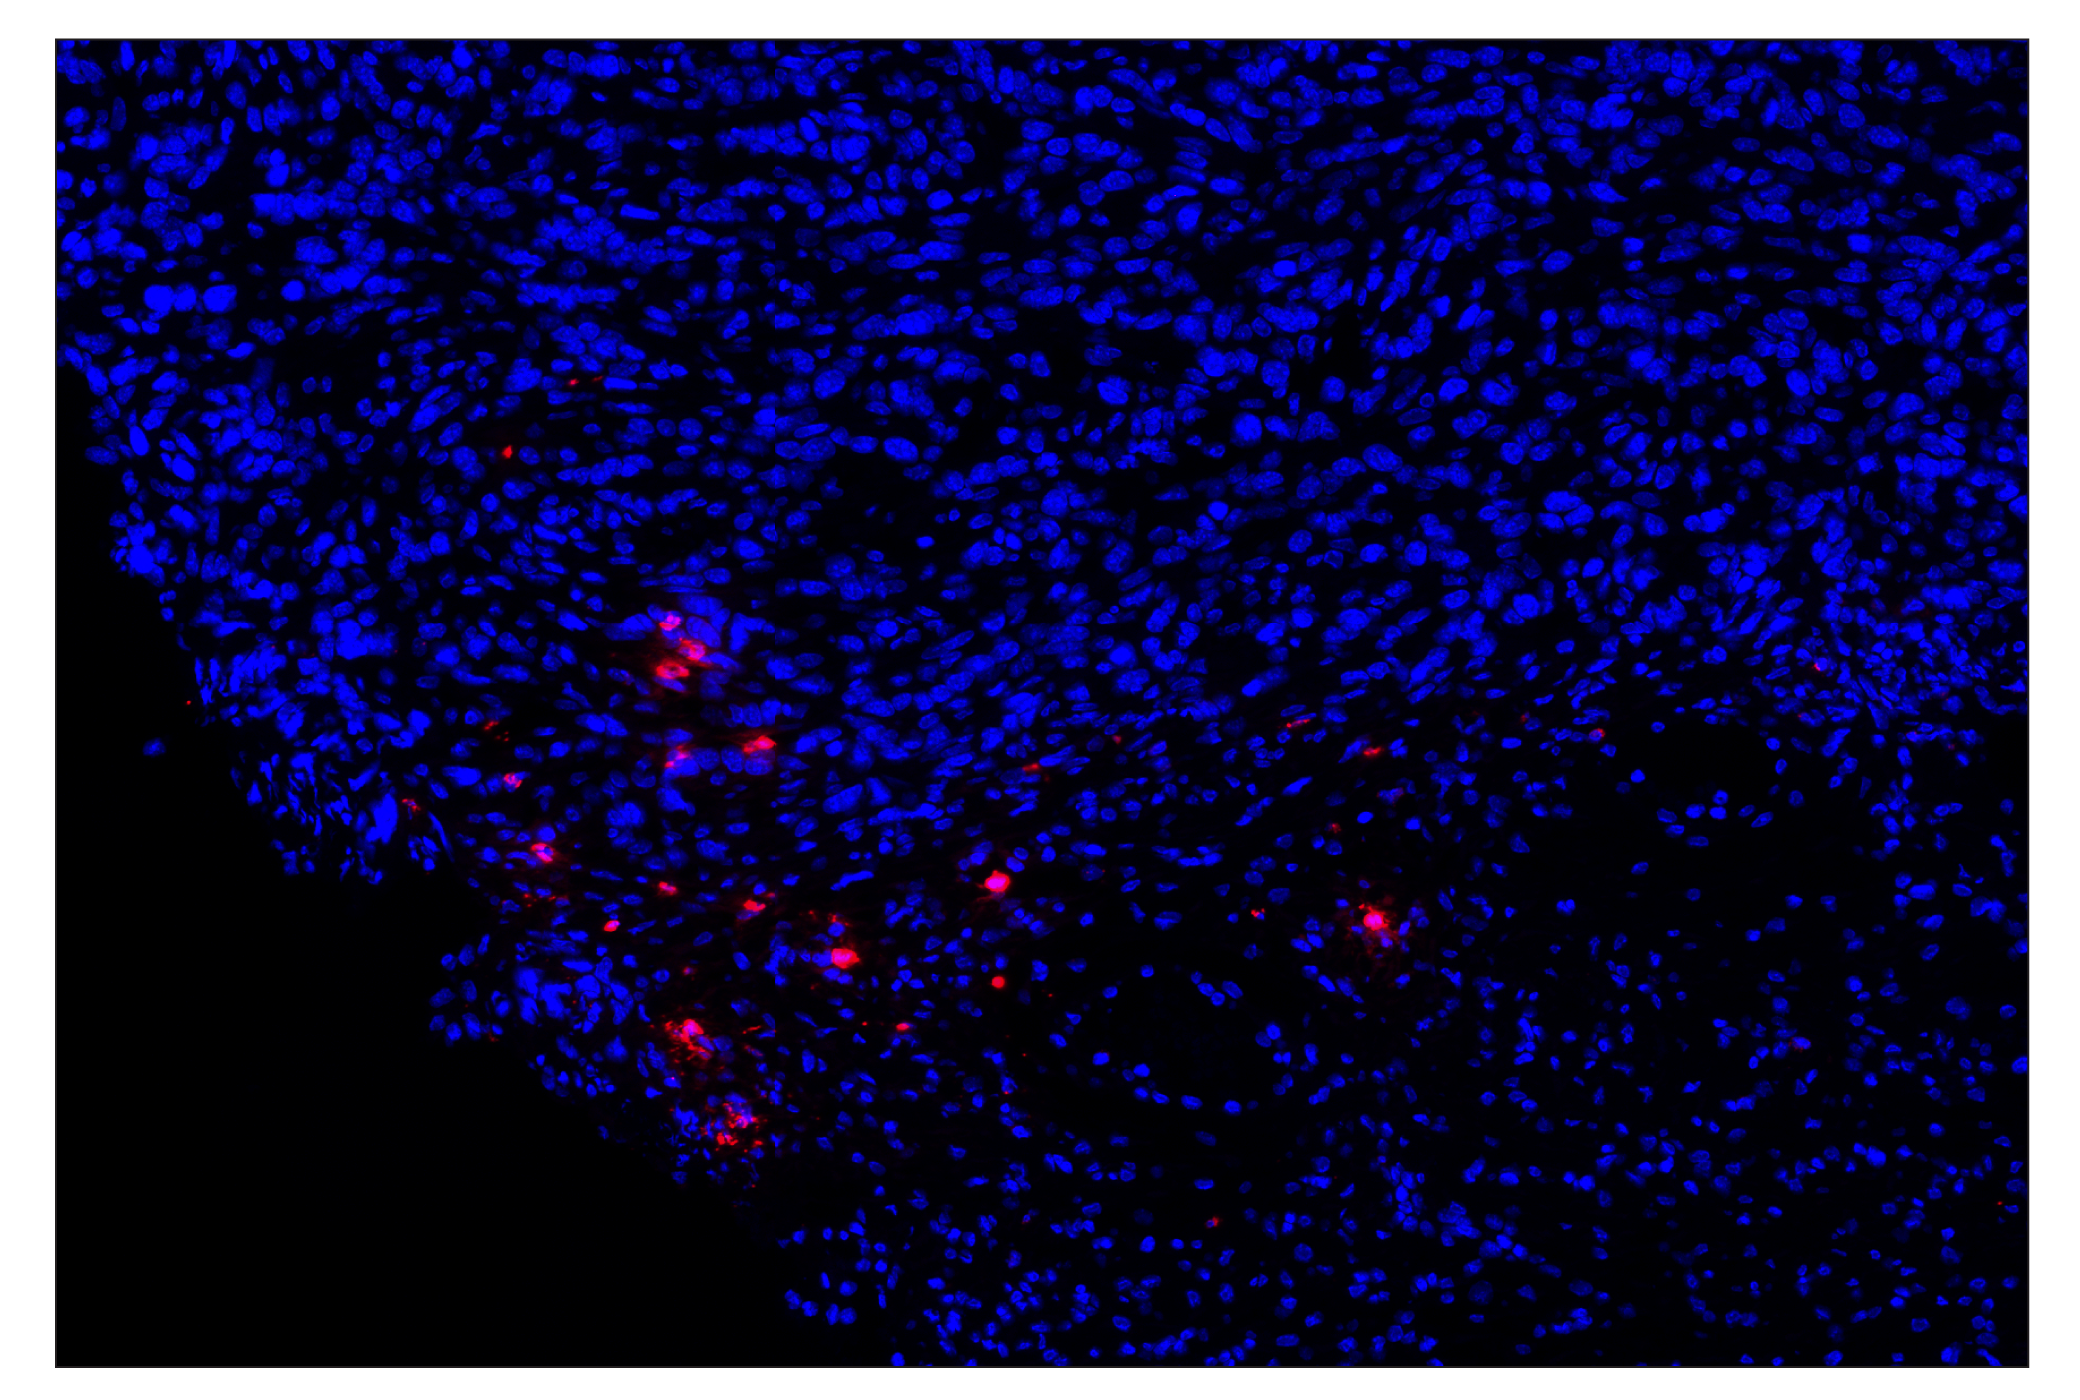

Eosinophil cationic protein (F3G7N) & CO-0230-488 SignalStar® Oligo-Antibody Pair

| Eosinophil cationic protein (F3G7N) Rabbit Monoclonal Antibody (SignalStar® Conjugate 0230) | 53231 | 50 µl | M | Rabbit IgG |

| Complementary Oligo (CO-0230-488) | 75688 | 30 µl |

SignalStar Oligo-Antibody Pairs are compatible with the SignalStar Multiplex IHC Buffer Kits for use in fluorescent multiplex imaging experiments. This product includes the oligo-conjugated antibodies and complementary oligos required for labeling your target protein on up to 10 slides. SignalStar Multiplex IHC Buffer Kits are required to amplify and image the target signal. Multiple oligo-antibody pairs can be conveniently combined into a multiplex panel using the SignalStar Multiplex IHC Panel Builder. SignalStar Multiplex IHC Kits & Reagents are not compatible with all of Cell Signaling Technology® products and protocols that are recommended for use in immunohistochemical assays.